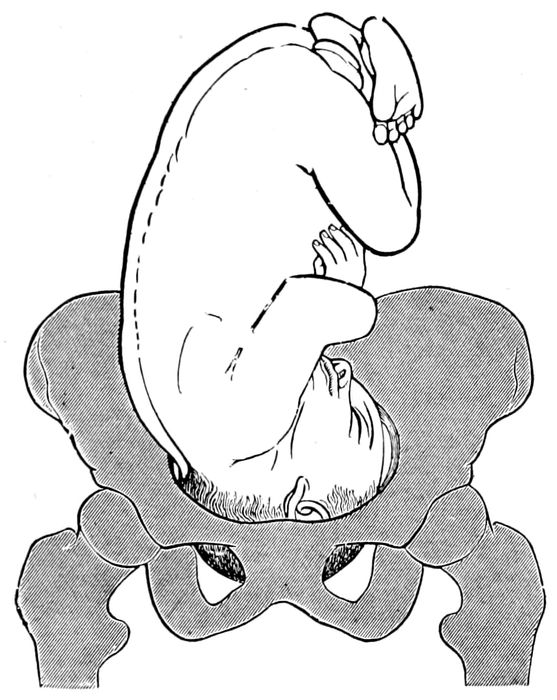

Fig. 20.—Normal attitude of fœtus (complete flexion). (Barbour.)

During development, the movements of the child become

observed. Gradually the child assumes a definite attitude

in the uterus. It becomes more and more folded

and flexed to accommodate its size to the limitations of

space. The head bends on the chest, the arms are

folded, the thighs flex against the abdomen, the legs

on the thighs, and even the back ultimately becomes

convex. It attains a complete flexion, the normal attitude

of the child. As maturity approaches, the head

becomes more and more palpable and seeks its usual location

in the lower pole of the uterus, resting on the

pelvic brim.